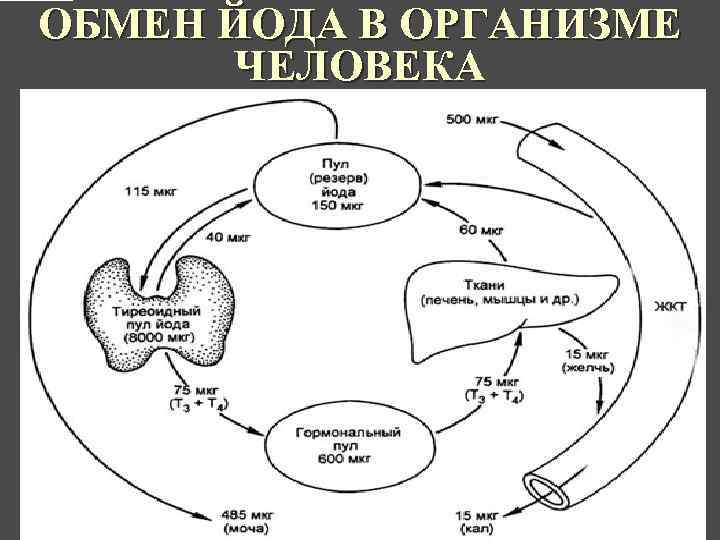

ОБМЕН ЙОДА В ОРГАНИЗМЕ ЧЕЛОВЕКА КАФЕДРА ХИРУРГИИ МОСКОВСКОГО ФАКУЛТЕТА